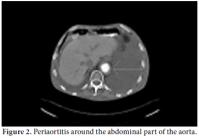

A 61-year-old male patient was admitted to our outpatient unit with dyspnea, edema on the legs, and chest pain. The physical examination was unremarkable except for exophthalmos, tachypnea, S3 edema, and bilateral pretibial pitting edema, and the laboratory investigation revealed the following levels: blood urea nitrogen 94 mg/dL, creatinin 1.38 mg/dL, and C-reactive protein (CRP) 1.53 mg/dl. The anti nuclear antibody (ANA) revealed a negative result. The globulin levels were within normal limits; therefore, IgG and E levels were not analyzed. The patient had no history of autoimmune or allergic diseases. An echocardiographic evaluation was performed to rule out heart failure and massive pericardial effusion, and a mass at the right atrial wall was detected. Nearly 1500 cc pericardial fluid was aspirated by pericardiosynthesis for the relief of the dyspnea. The examinations for tuberculosis revealed negative results, but atypical mesothelial and inflammatory cells were seen in the cytological evaluation. Therefore, computed tomography (CT) of the abdomen and thorax was ordered for further evaluation and pericardial effusion and periaortitis was detected beginning from the arcus and lasting to the abdominal aorta (Figures 1 and 2). On the cardiac CT scan, three soft tissues arising from the right coronary artery and extending to the right atrium were seen (Figure 3). The serologic tests for perinuclear anti-neutrophil cytoplasmic antibodies (p-ANCA) and cytoplasmic anti-neutrophil cytoplasmic autoantibody (c-ANCA) were negative. The radiological evaluation of the exophthalmos with cranial CT revealed bilateral retro-orbital pseudotumors, although the thyroidstimulating hormone level was normal (Figure 4). By all of these radiological findings, IgG4-related sclerosing vasculitis was first suspected, and the level of IgG4 was found to be 148 (0-125) U/ml. The patient was referred to the cardiovascular surgeons for a biopsy from the mass in the right atrium. The histological evaluation of the biopsy material revealed lymphoplasmacytic infiltration fibrosis, a lymphoid follicle, and eosinophilic infiltration. These findings were concordant with IgG4-related sclerosing vasculitis. The arterial constrictions in the right coronary artery and circumflex artery were removed by percutaneous balloon angioplasty and two cardiac stents a cardiac pacemaker were implanted.

The appropriate treatment was ordered as a pulse steroid of 1000 mg prednisolone and 500 mg cyclophosphamide every month in conjunction with oral immunosuppressive therapy. A radiological evaluation after three months revealed significant response and regression of the lesions. The mass in the right atrium had decreased to 16 mm, and the lesion on the retro-orbital area had decreased to 11 mm on the right and 12 mm on the left.